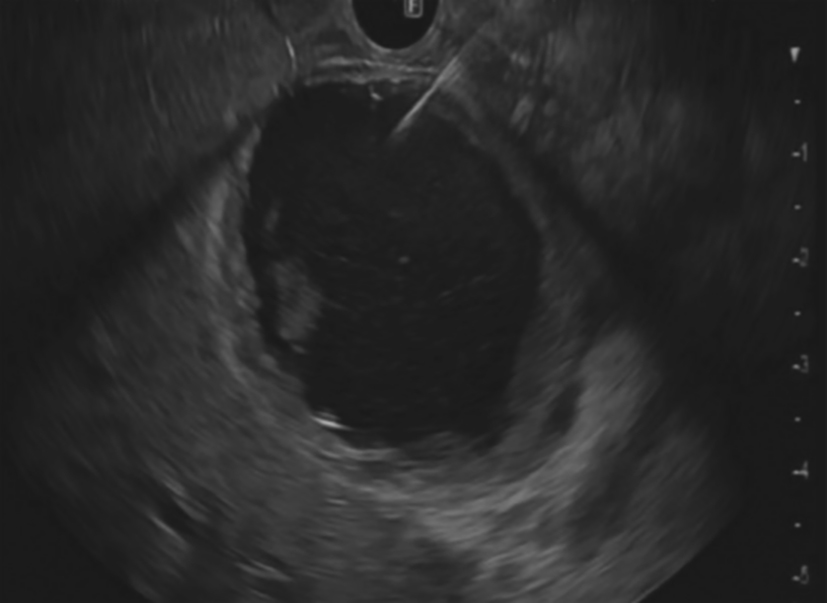

3. Development of the puncture channel. Over the past 10 years, endoscopic ultrasonography (EUS) has gradually become the third eye for endoscopists. Its combination with SMIS brings a new type model for the diagnosis and treatment of organic lesions outside the digestive tubes. For example, EUS-guided bile drainage (EUS–BD) and EUS-guided pancreatic duct drainage (EUS–PD) have been used as effective treatments after the failure of trans-nipple drainage; meanwhile the treatment strategy for acute necrotizing pancreatitis has also changed greatly. EUS-guided super minimally invasive drainage by gastric parietal puncture for pancreatic encapsulated necrosis and EUS-guided pancreatic cystic lesion puncture laurosinol ablation have become the mainstream treatment methods. In the future, SIMS operations like exploring and refining super minimally invasive drainage via a gastric puncture channel for suppurative cholecystitis, EUS-guided super minimally invasive gallstone extraction via a gastric puncture channel, EUS-guided portosystemic shunts and EUS-guided drainage of the chest, the abdomen and pelvic abscess, etc. will be the development directions.

Gastrointestinal endoscopic super minimally invasive surgery (eSMIS) is a branch of SMIS operations. After multiple years of development and clinical practice, presently eSMIS has a perfect endoscopic technique, a nomenclature of procedures and implementation principles, as well as specific development perspectives. Over the recent 10 years, endoscopic scholars in China have been constantly innovating and developing a series of SMIS surgical methods according to four directions, namely, natural, tunnel, puncture, and multi-cavity channels. For example, in the SMIS operation of early gastric cancer, full-thickness resection of the lesion by natural channel, full-thickness resection by multiple-cavity + lymphadenectomy approaches, the technique of sealing large wounds after non-full-thickness resection, and the traction technique in non-full-thickness resection; in the treatment of large-area early esophageal cancer by tunnel channel, autologous skin graft was used to prevent esophageal stenosis after large esophageal defect, and for the diagnosis and treatment through the muscularis propria to the outside of the digestive lumen; some breakthroughs in SMIS operations of the bile pancreatic disease, including laser lithotripsy under direct choledochoscope with sphincter preserved, exploratory pancreatic duct with cholangiopancreatic vision system, super minimally invasive photodynamic therapy under pancreatoscope, radiofrequency ablation of bile duct under direct choledochoscope, direct choledochoscopy with a duodenal papillary support for the extraction of gallbladder silt stones and of biliary calculus, etc., have been achieved.